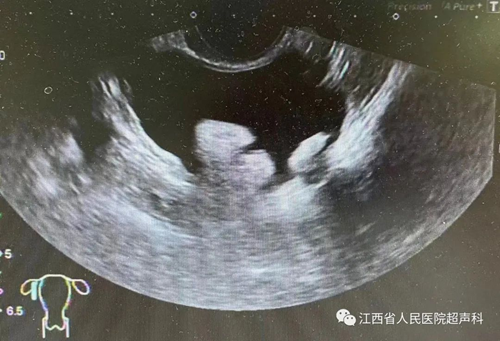

超声检查是卵巢囊肿最常用的检查方式,有性生活史者建议首选经阴道超声检查,无性生活或囊肿过大超出盆腔也可选择腹部超声检查。超声显示囊肿呈囊性无回声、囊壁薄、无实性成分、无分隔及血流信号者称为单纯囊肿。

超声显示囊肿内部有分隔伴异常回声称为单房性/多房性囊肿。